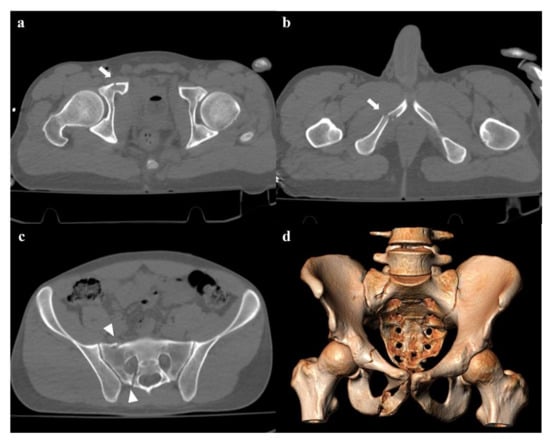

• Grade 1: compression fracture of the sacrum on the side of the impact, and transverse fracture of unilateral or bilateral pubic branches (Figure 1). Lateral compression grade 1 injuries are stable and have a nonoperative management [3].

• Zone II: the fracture involves the neuroforamina (Figure 1). In 28% of cases, there is an ipsilateral neurological deficit.

Figure 1. Lateral compression fracture, type 1. Axial computed tomography (CT) images show a fracture of the right-side superior and inferior pubic rami (arrows in (a,b)), and ipsilateral fracture of the sacrum (arrowheads in (c)); the sacral fracture involves the neuroforamina (zone II). Three-dimensional volume-rendering CT reconstruction in anteroposterior (AP) view confirms the type of fracture (d).